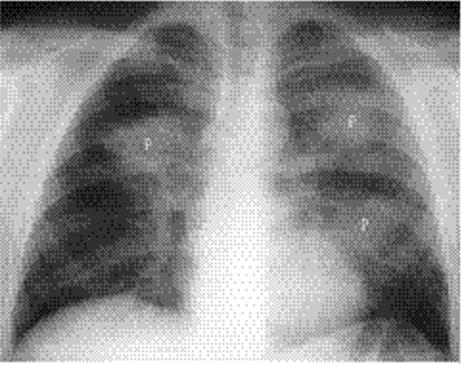

Nodular or spherical pneumonia is usually due to pneumococcal, Legionella, Q fever, or fungal pneumonia. Hematogenous dissemination ofS. aureus can cause spherical pneumonia or septic emboli. Reticulonodular opacity and peribronchial thickening are typical of viruses andMycoplasma.

Round pneumonia: Some pneumonias have this configuration initially. There is usually an ill-defined border (Fig. 5.11). Air bronchograms are frequently present.